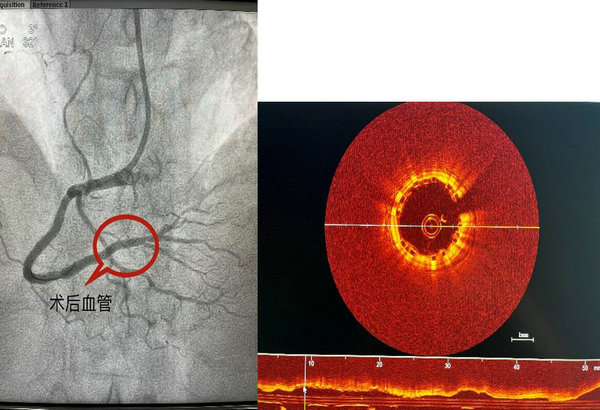

53岁的马女士家住讷河市,平素身体状况良好,无高血压、糖尿病病史,无吸烟、饮酒等不良嗜好,入院前一个月开始出现与活动劳累相关的胸骨后疼痛,伴有肩膀放射痛,持续数分钟后症状可逐渐缓解,为求诊治来到心血管内科三区。患者虽无明确冠脉病变易患因素,但心绞痛症状典型,入院后安排完善冠脉造影检查,结果显示患者右冠状动脉中远段99%狭窄,且病变局限,其余血管未见明显狭窄及钙化。结合患者实际情况,吴晓杰主任决定给予患者可吸收支架植入治疗,术前术后给予OCT检查,精准评估病变长度及管腔内径,OCT检查结果显示支架膨胀良好,无贴壁不良;管腔面积恢复满意,手术过程顺利。

术后影像图